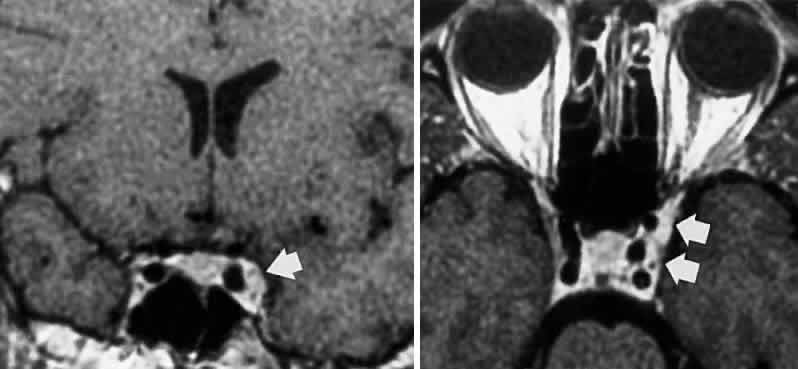

FASCICULAR LESIONS Deficits of the oculomotor fasciculus are usually identified by the accompanying brain stem signs. Oculomotor palsy with contralateral hemiplegia (Weber syndrome) indicates involvement of the corticospinal tracts. Contralateral ataxia and intention tremor (Benedikt syndrome) indicates involvement of the red nucleus (see Fig. 2). Nothnagel syndrome is an eponym given when signs of both Weber and Benedikt syndromes are present. Midbrain vascular accidents account for most fascicular defects. Ksiazek84 shed some light on the fascicular arrangement of the oculomotor nerve based on two patients with partial oculomotor paresis, each with pupillary mydriasis, significant inferior rectus paresis, and medial rectus paresis. Neuroimaging revealed a lesion in the fascicular portion of the nerve, thus indicating the proximity of these fibers in the fasciculus. Monocular elevator paresis (superior rectus and inferior oblique) in mass compression of the oculomotor fasciculus has also been reported.85 In this regard, Castro and associates86 proposed the mediolateral somatotopy of the oculomotor fascicular fibers within the mesencephalon with the inferior oblique and superior rectus muscles being most lateral, and the pupilloconstrictor fibers and inferior rectus being most medial. The levator palpebrae fascicles are in an intermediate location between the superior rectus and medial rectus fascicles. INTERPEDUNCULAR LESIONS Basal lesions, including the rare rostral basilar artery aneurysm, may encroach on the oculomotor nerves as they exit in the interpeduncular space. Such slow-growing aneurysms, either saccular or fusiform, may present as partial oculomotor palsies with or without involvement of pyramidal tracts, and without subarachnoid hemorrhage.87 Aneurysms of the posterior communicating artery, on the other hand, are probably the most common lesions causing acute spontaneous oculomotor palsies (Fig. 12). According to Hyland and Barnett,88 the oculomotor palsy that occurs with posterior communicating aneurysm is not necessarily due to mass effect per se, but rather is attributed to hemorrhage that suddenly enlarges the aneurysmal sac to which the oculomotor nerve is adherent, or to hemorrhage into the substance of the nerve itself. Most patients present, therefore, with an intensely painful, complete unilateral oculomotor palsy in association with other signs and symptoms of subarachnoid hemorrhage. Few patients with symptomatic posterior communicating aneurysms are found in office waiting rooms: they are usually obtunded or comatose in emergency rooms. Involvement of pupillary fibers is such a consistent finding in third nerve palsies due to bleeding aneurysms that most clinicians concur in this useful dictum: a pupil-sparing, but otherwise complete, third nerve palsy is very unlikely to be due to posterior communicating aneurysms. Careful pupil evaluation may disclose subtle abnormalities in “apparent pupil-sparing,” especially in cases of aberrant regeneration or with chronic cavernous sinus lesions. Generally, in patients at least 50 years of age or older, an acute, isolated, painful oculomotor palsy that spares the pupil is caused by intraneural ischemia; nevertheless, these patients must be carefully observed for further evolution. In our opinion, an acute complete oculomotor palsy with moderate to major mydriasis, even when diabetes is present, is an indication for cerebral arteriography. It should be emphasized that magnetic resonance angiography may not detect aneurysms smaller than 3 to 4 mm.89 The clinical management of patients with relative pupil-sparing third nerve palsies remains in debate. Observation alone arguably is appropriate management of such patients; however, since practically every conceivable combination of partial ophthalmoplegia and pupillary abnormality has been reported in aneurysmal compression of the third nerve, it is better to err on the side of caution and perform angiography more frequently. It is incumbent upon the physician to evaluate carefully the proportion of ophthalmoplegia and ptosis in relation to the degree of pupillary abnormality when deciding appropriate workup of these patients. Again, the increasing sensitivity of magnetic resonance angiography has not yet entirely replaced formal angiography. Certainly, neurosurgical intervention requires conventional cerebral arteriography before surgical treatment. Capó and colleagues90 pointed out that the interval from onset to maximal ophthalmoplegia does not differentiate between microvascular (3.3 days) and aneurysm (3 days), but that failure to recover within 4 to 8 weeks requires further evaluation. Other partial oculomotor palsies occur regularly with cavernous sinus masses and parasellar syndromes (see below), accompanied by variable pupillary findings. Furthermore, both acute and chronic lesions may produce incomplete palsy of the superior division (supplying levator palpebrae and superior rectus muscles) or of the inferior division (medial and inferior recti, inferior oblique and pupillomotor fibers). If pain or first trigeminal division numbness are absent, and if the pupil is uninvolved, such fractional oculomotor pareses are regularly misinterpreted as myasthenia or local orbital inflammations. Guy et al91 described five patients with isolated ptosis and elevator paresis in abduction, consistent with selective “superior division” involvement. They also discussed five previously reported cases with the following respective diagnoses: (1) intracavernous aneurysm (usually with associated Horner's syndrome) and basilar artery aneurysm; (2) diabetic ophthalmoplegia; (3) meningitis; (4) dural lymphoma; and (5) postsurgical manipulation of parasellar structures. In essence, there was little anatomic correlation with the physical separation into superior and inferior oculomotor trunks that occurs in the cavernous sinus. Moreover, two patients sustained superior division palsies during surgical manipulation of the subarachnoidal portion of the oculomotor nerve trunk. A number of cases of inferior rectus paresis, isolated or in combination with ipsilateral or contralateral superior rectus paresis, have been construed as focal lesions involving the rostral portion of the oculomotor nuclear complex.80–82 Oculomotor palsy following head trauma is not rare, but probably occurs less frequently than traumatic fourth nerve palsies. As a rule, such closed-head injury causes loss of consciousness and is accompanied by skull fracture, but this is not invariable. Injury to the ocular motor nerves in road accidents was studied by Heinze,92 who dissected the cadavers of 21 fatal cases. He found that the relationship of frontal or temporal fractures to neural damage was unpredictable. In fact, intact nerves were encountered adjacent to gross fracture sites. The oculomotor nerve was damaged at three locations: (1) avulsion of the rootlets at their ventral exit from the brain stem; (2) contusion necrosis of the most proximal portion of the nerve trunk; and (3) intraneural and perineural hemorrhage of the nerve trunks at the level of the superior orbital fissure. Of great interest are Heinze's findings of focal hemorrhages in extraocular muscles, usually associated with fractured orbital bones. Eyster et al93 reported three patients with large basicranial tumors, who presented with oculomotor palsies precipitated by mild blows to the head that were insufficient to cause fracture or loss of consciousness. The oculomotor nerves were encased and stretched by tumor, which apparently rendered these tethered nerves vulnerable when innocent head blows abruptly shifted the brain. The authors pointed out that such atypical presentations of intracranial tumors may further mimic aneurysms, since subarachnoid hemorrhage does occasionally occur with tumors. Neetens94 reported an additional three cases of oculomotor nerve palsies after minor trauma in the presence of basal intracranial tumors; the trochlear nerve was involved in all three cases, and in two cases the oculomotor nerve was partially affected. Walter et al95 reported two instances of minor head trauma resulting in complete third nerve palsies attributed to occult posterior communicating artery aneurysms. We have seen a 45-year-old school teacher who experienced an immediate right abducens palsy when playfully slapped on the back of the head; within weeks, other cranial nerve palsies announced the presence of diffuse meningeal spread of carcinoma. In the United States, basilar meningitis is rare, but was formerly encountered with tuberculosis and syphilis. When the third nerve is involved in such cases, progressive defects are the rule and other cranial nerve palsies are commonly found. Oculomotor palsy may especially occur with meningitides in infants, including instances of viral and bacterial (e.g., Streptococcus pneumoniae, Haemophilus influenzae) infections.96 Oculomotor nerve compression by the proximal segment of the posterior cerebral artery, or by the uncus against the petroclinoid ligament, can be seen with increasing cerebral edema or with an ipsilateral expanding supratentorial mass, and it is often heralded by unilateral pupillary dilation (Hutchinson pupil). Progression rapidly leads to complete ocular motor nerve palsy. Keane97 reviewed the ocular motor signs of tentorial herniation, which include anisocoria and parasympathetic pupillary abnormalities, unilateral or bilateral ptosis, internuclear ophthalmoplegia, vertical gaze paresis, and partial third nerve palsies. CAVERNOUS SINUS LESIONS The oculomotor nerve may be involved by inflammatory disease, tumor, aneurysm, arteriovenous fistula, or thrombosis at the level of the cavernous sinus. The third nerve is usually involved in combination with the fourth, sixth, and ophthalmictrigeminal nerves, and accompanying sympathetic paresis may minimize pupillary dilation. The syndrome of the cavernous sinus, therefore, includes multiple ocular motor nerve palsies and pain or numbness in the first trigeminal division. In practice, lesions involving primarily the superior orbital fissure produce signs and symptoms that, with the possible exception of proptosis, cannot be distinguished from those of the anterior cavernous sinus. In particular, dural carotid cavernous fistulas that drain primarily into the inferior petrosal sinus may cause third nerve pareses without significant orbital congestion.98 Third nerve palsies due to lesions in the cavernous sinus tend to be partial in that all muscles innervated by the oculomotor branches need not be involved. This is especially true of pupillomotor fibers, such that the pupil may be normal or minimally involved. This “pupil- sparing” is offhandedly attributed to the superimposition of sympathetic paresis (Horner syndrome), but appropriate pharmacologic tests rarely substantiate this explanation (see below, Parasellar Syndrome). More likely, slowly expanding masses (e.g., infraclinoid aneurysm, meningioma) functionally spare the pupilloconstrictor fibers in the intracavernous portion of the oculomotor nerve. In addition, the levator, superior, inferior, and medial recti may be involved in unequal degrees, but progressive paresis evolves. (Once again, myasthenia must be suspected in any nonpainful, pupil-sparing, nonproptotic ophthalmoplegia, with or without ptosis.) Cavernous sinus lesions are further discussed below. Primary neurinoma of the oculomotor nerve is a relatively rare lesion that should be considered in children or young adults with insidious third nerve palsy. These may occur in the cavernous or interpeduncular portion of the nerve (Fig. 13).99,100